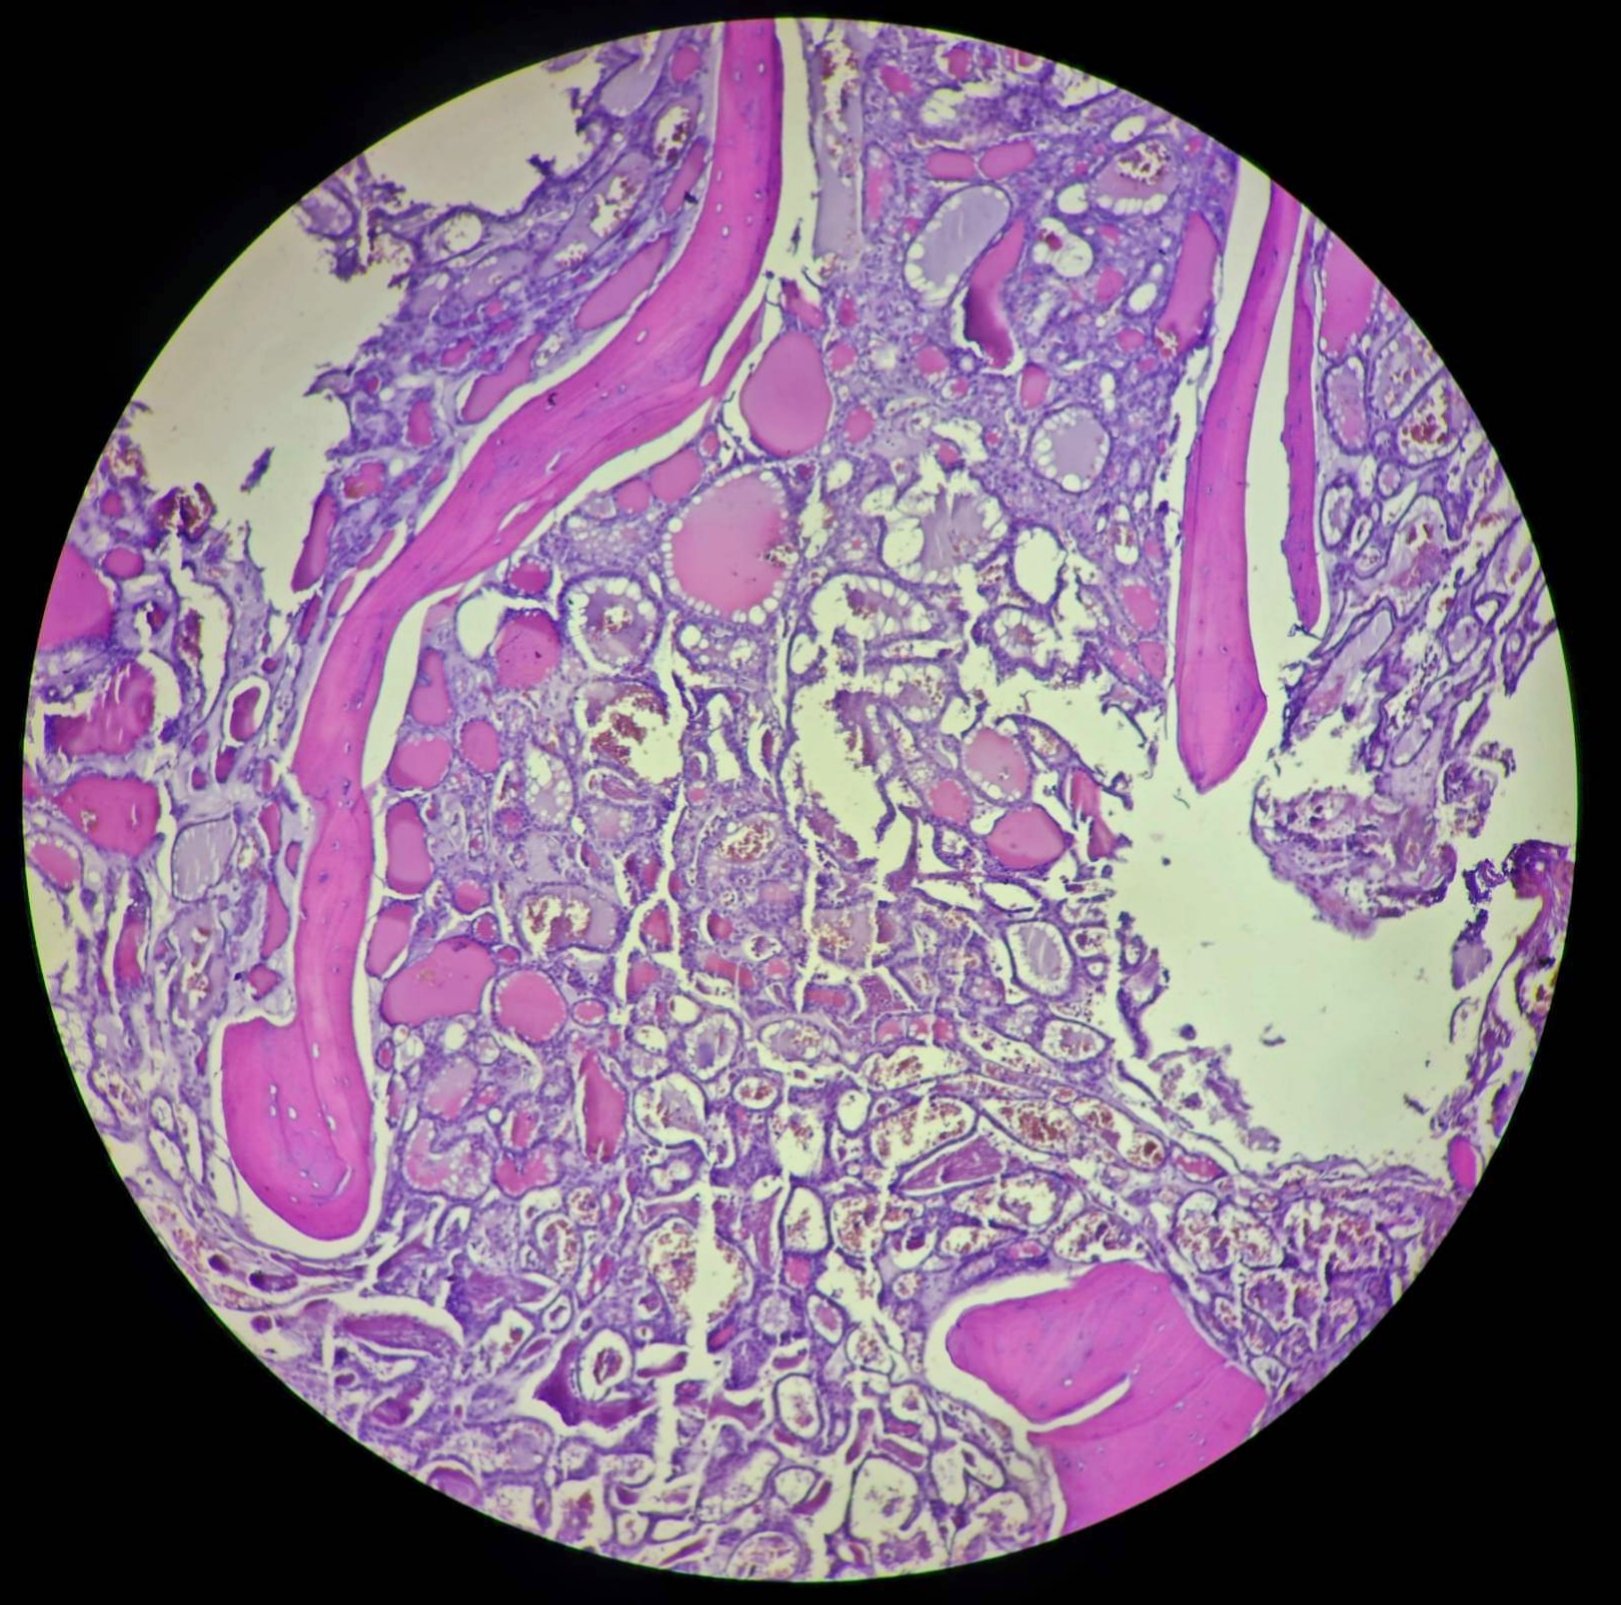

Bilateral tympanokeratomas (cholesteatomas) with bilateral ...